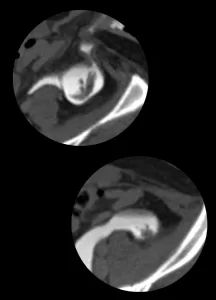

Fase nefrográfica

Fase excretora

Derivação urinária em alça delgada na fossa ilíaca à esquerda. Houve boa distensão da alça de derivação, porém nota-se falha de enchimento de aspecto polipoide na fase excretora medindo cerca de 2,2 x 1,0 cm. Sugere-se prosseguir investigação.